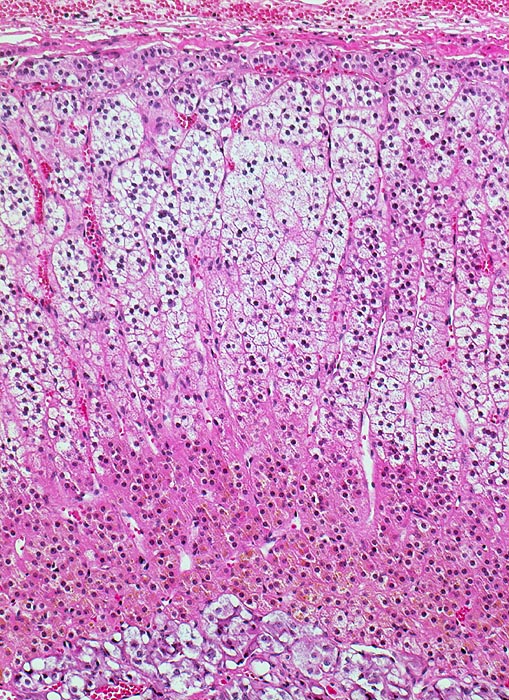

• Solide Tumorzellaggregate eingefasst von dünnen Bindegewebssepten mit zahlreichen dünnwandigen Blutgefässen.

• Polygonale Tumorzellen mit reichlich klarzelligem Zytoplasma und deutlichen Zellgrenzen.

• Hyperchromatische, polymorphe grosse Kerne mit prominenten Nukleolen (entspricht einem Grad 3 nach WHO/ISUP).